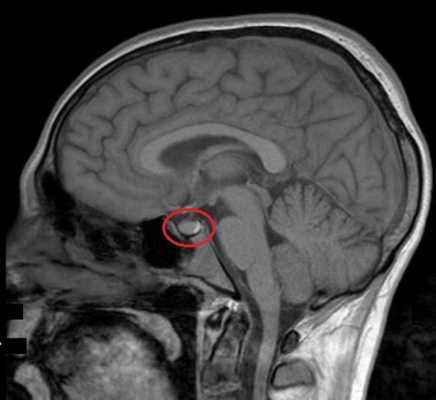

МРТ гипофиза с контрастом. После введения контрастного вещества в гипофизе происходит его накопления и он выглядит светлым. Только участок опухоли не накапливает контрастное вещество и выглятит темным (стрелка).